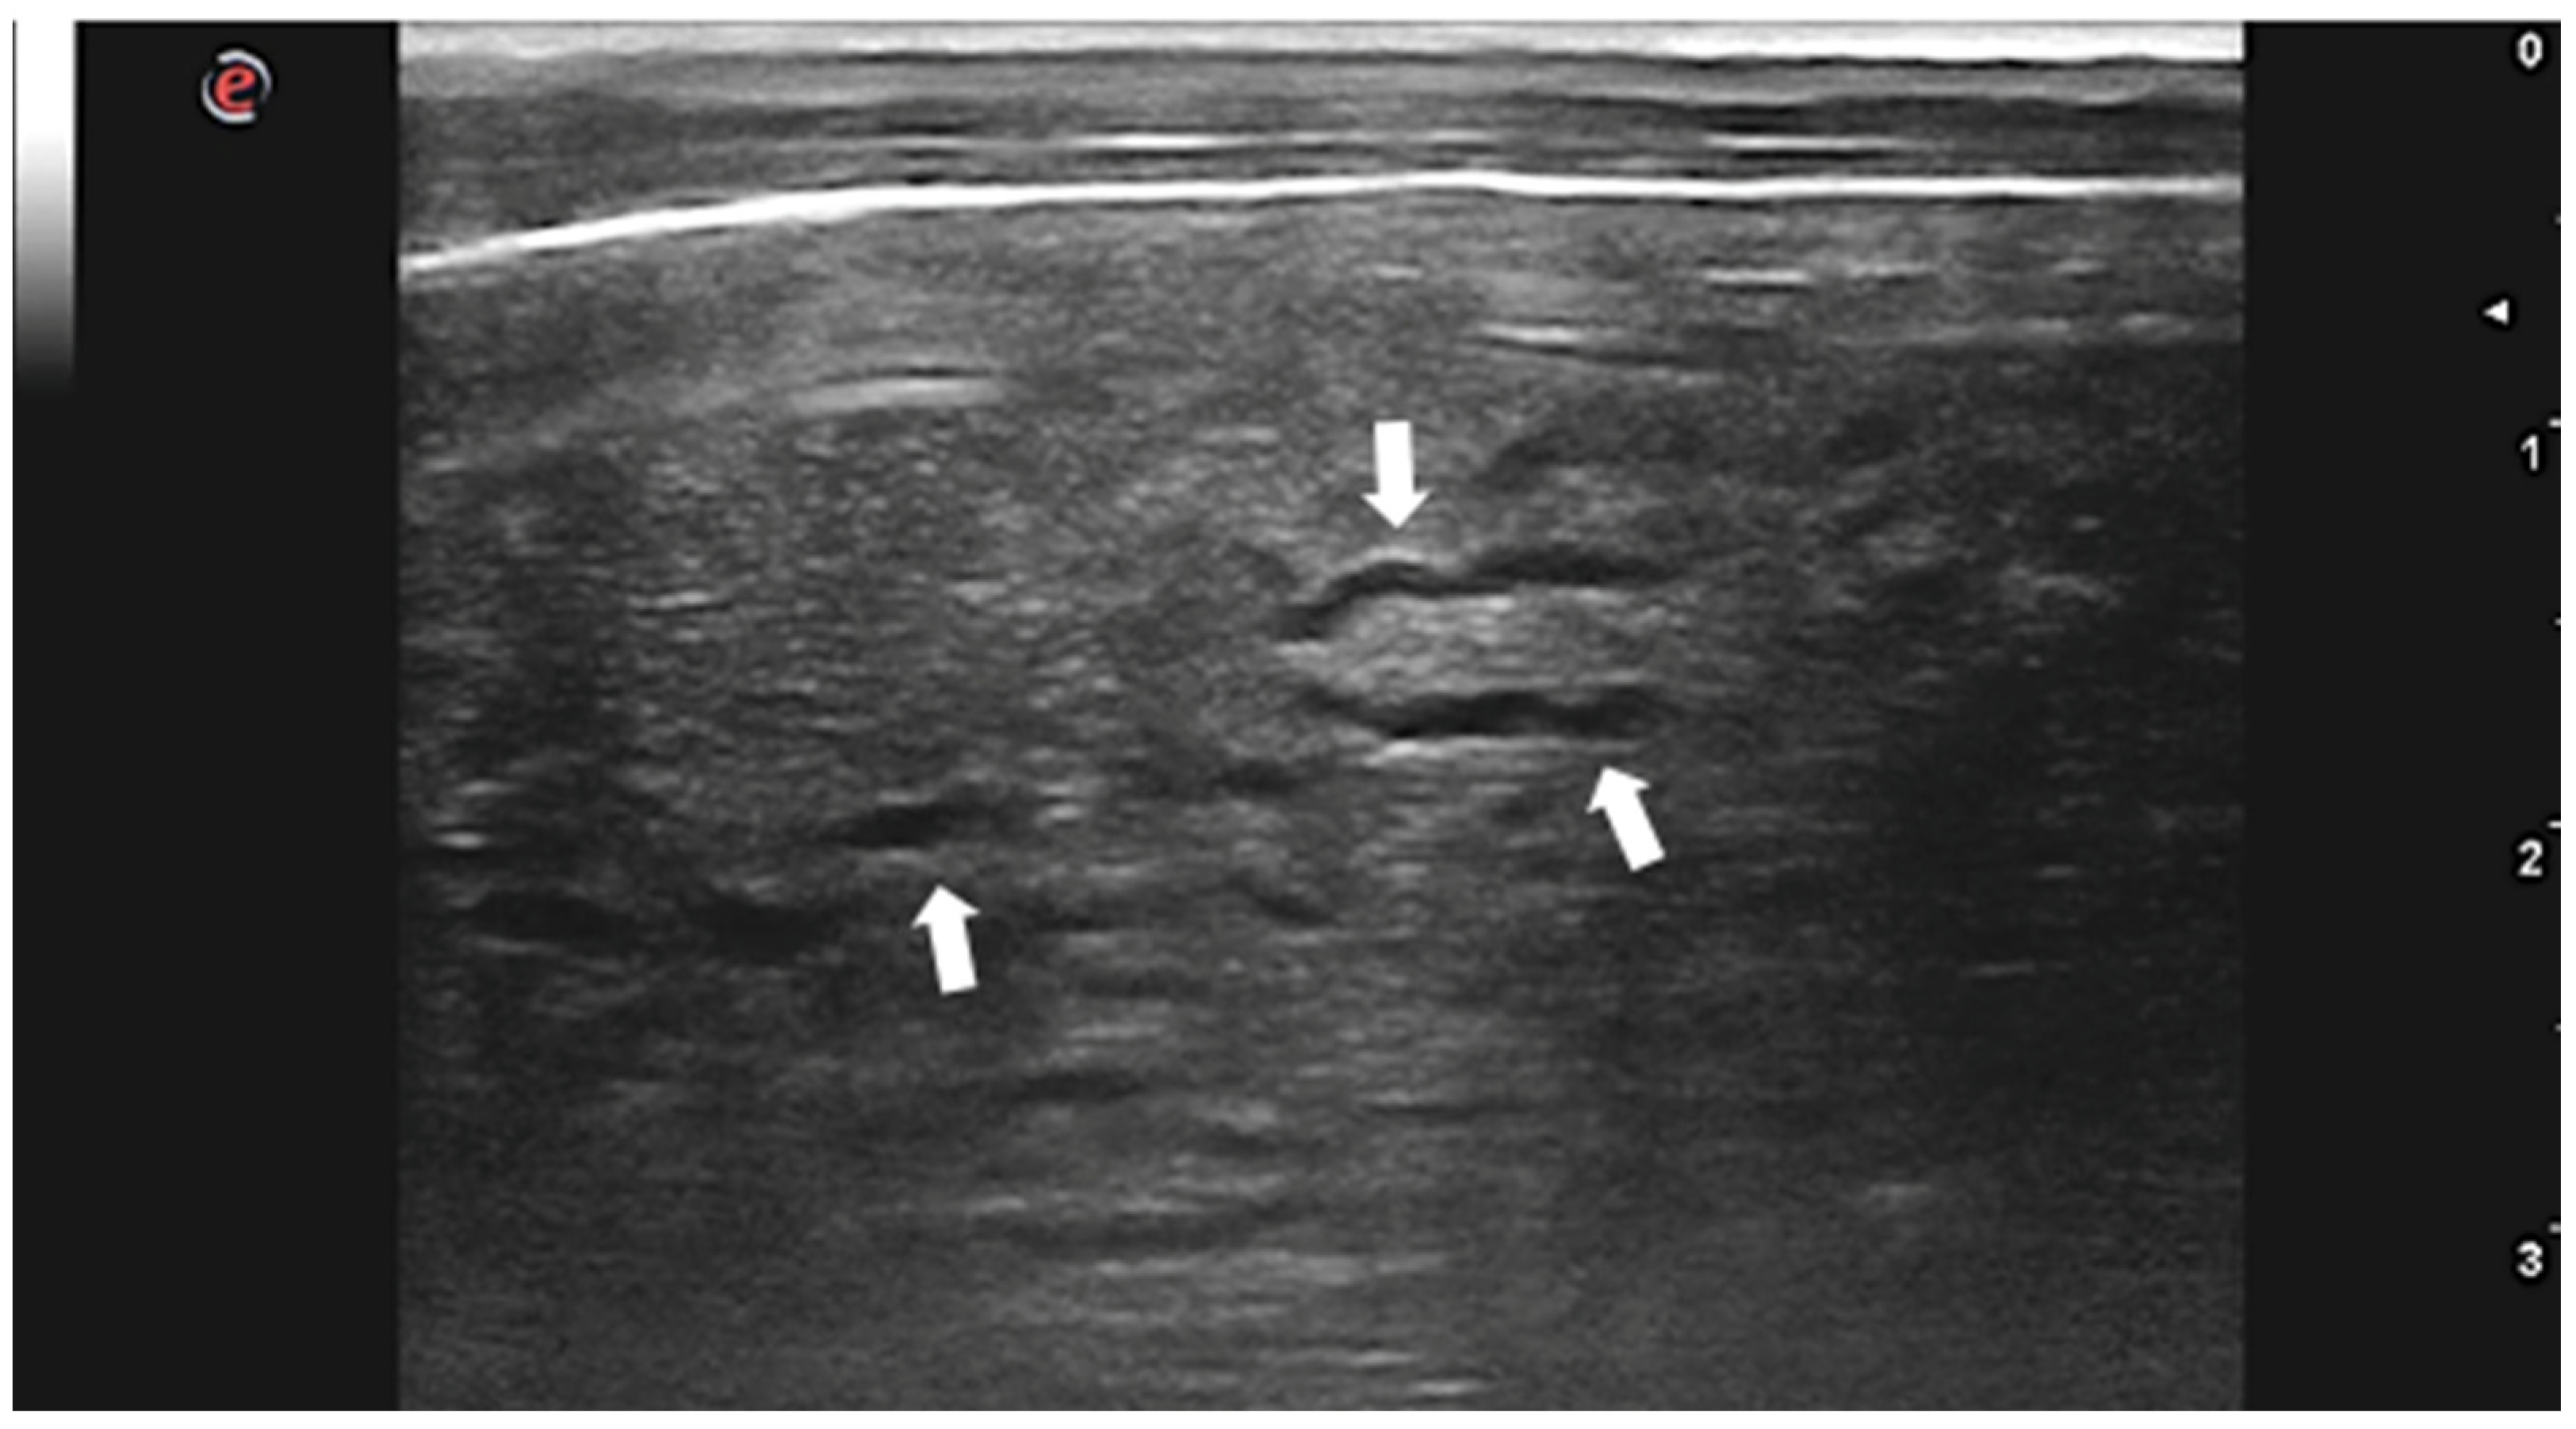

- Venco, L.; Colaneri, G.; Formaggini, L.; De Franco, M.; Rishniw, M. Utility of thoracic ultrasonography in a rapid diagnosis of angiostrongylosis in young dogs presenting with respiratory distress. Vet. J. 2021, 271, 105649. [Google Scholar] [CrossRef]